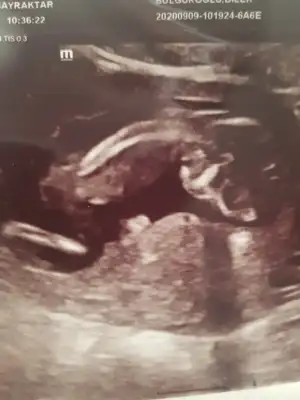

Ikra meyra Ikra meyra merhaba tatlı anne bize de bir tahmininiz olur mu bi türlü göremedik 🙈😁🥰

Eklentiler

• 262AEF80-5FD5-43DA-93AB-832943ADA823.webp

262AEF80-5FD5-43DA-93AB-832943ADA823.webp

29,6 KB · Görüntüleme: 102